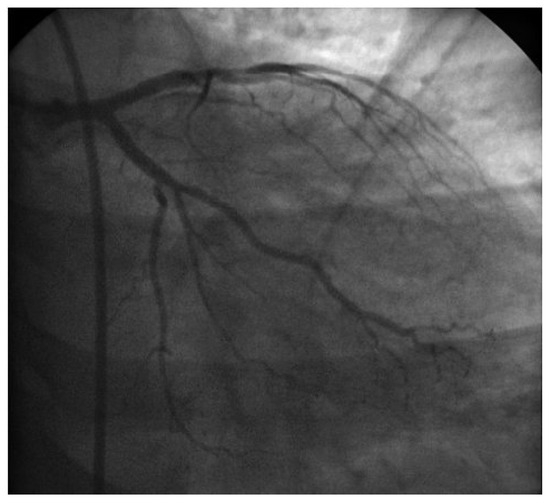

Case report